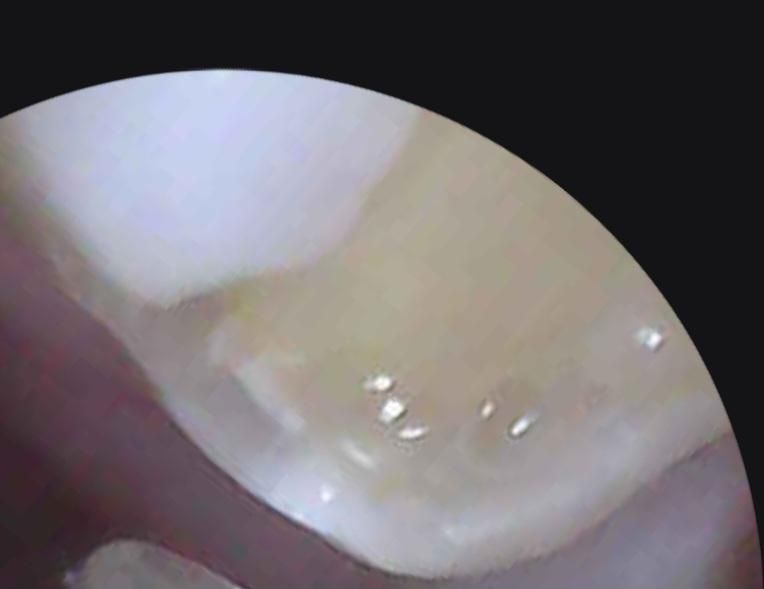

저번에 충치 레진치료했던 어금니가 깨졌어요.

19살 학생인데 예전에 충치 치료한지는 좀 됐구요. 오늘 껌 먹다가 치료한 어금니 옆면이 조금 많이 깨져서 내일 치과 가려고 하는데 이정도면 신경치료 안하고 인레이나 크라운 씌우려나요? 사진으로 봤을 때 충치는 없어 보이는데.. 통증도 정말 약하게 시린정도? 정말 신경치료안하고 싶어요 ㅠㅠ

• 2번 째 사진

치아를 너무 가깝게 촬영하여 잘 구분이 안갑니다. 다만 충치는 없어보이고 단순히 떨어져나간 것으로 보여 신경치료는 하지 않을 것 같습니다.

정확한 건 방사선 사진을 찍어봐야 합니다. 충치는 없고 깨지기만 했다면 기존 수복물 제거하고 다시 똑같은 방식으로 재치료해주면 될 것 같습니다.